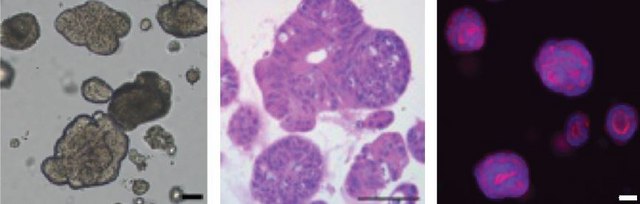

Colorectal cancer accounts for roughly 10% of all cancer cases worldwide with more than half of all patients with CRC developing metastatic disease leading to death. Recently, tissue derived organoids have emerged as a more predictive 3 dimensional cell culture model of disease. 3D organoid cultures conserve the original genetic and phenotypic characteristics of the primary tissue allowing for their application in many research fields included drug development, personalized medicine and potential therapeutics. In vitro cultured tumor organoids have also been shown to predict patient response to chemotherapeutics. PDOs derived from colorectal cancer (CRC organoids) have been used for cell modeling and to investigate the function of cancer related driver gene mutations including APC, TP53, KRAS, BRAF, PIK3CA etc.

3dGRO® Human CRC Organoids are offered in a ready-to-assay format intended to simplify the organoid cell culture workflow. A single vial of organoids is enough to directly thaw and seed into a 96-well plate without cell expansion for drug screening applications. The organoids are manufactured using Cellesce′s patented technology which enables the robust growth and expansion of patient-derived organoids (PDOs). Cellesce′s technology minimizes manual handling time to maximize reproducibility in order to position organoid cell models as a cost effective and accurate tool in early-stage drug discovery. The organoid biobank includes tumor derived colorectal cancer PDOs from a range of genetic backgrounds, driver gene mutations, tumor sites and cancer stages. These organoid cell lines have been well characterized and are all validated for response against a number of known CRC-targeting agents.

Ready-to-Assay human colorectal cancer organoids for 3D cell culture applications.